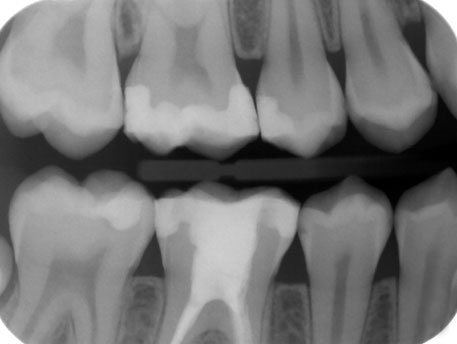

RX. Bitewing